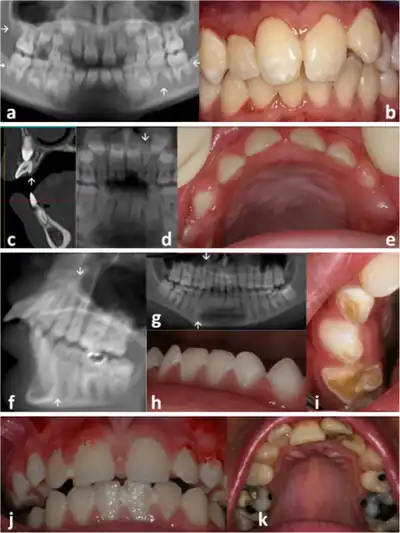

| Face | Wizened faceies. Sunken eyes, large ears, thin pointy nose. Small chin. Dental caries, enamel hypoplasia | |